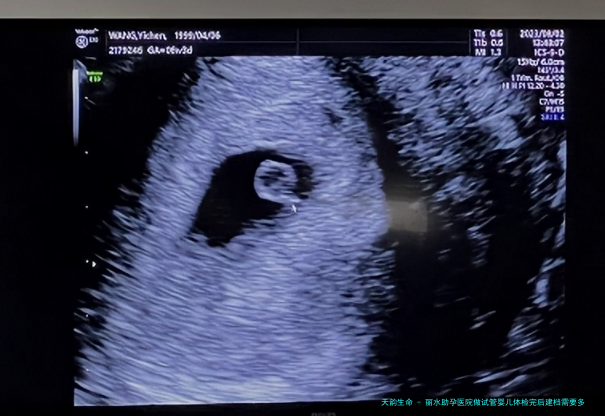

我是患有多年的多囊卵巢,尽管一贯在服药调理,但是要么没有多大的作用,因而如今我和丈夫决定去做试管婴儿怀孕,此刻我们已经在丽水市助孕医院建完档案了,医生告诉我们让1天其后医院定方案,我们想问一下一般在建完档之后做试管还要准备好多钱才够呢?

丽水市助孕医院是一家三级甲等的综合性医院,是现在丽水市仅有一家能够发展试管婴儿技术的医院,每年都有许多试管助孕病人去往这家医院做试管,所以所有人也比较关心该医院生殖医院做试管的相关费用,下面列举是该医院做试管每个阶段的费用明细,详细下述所展示: